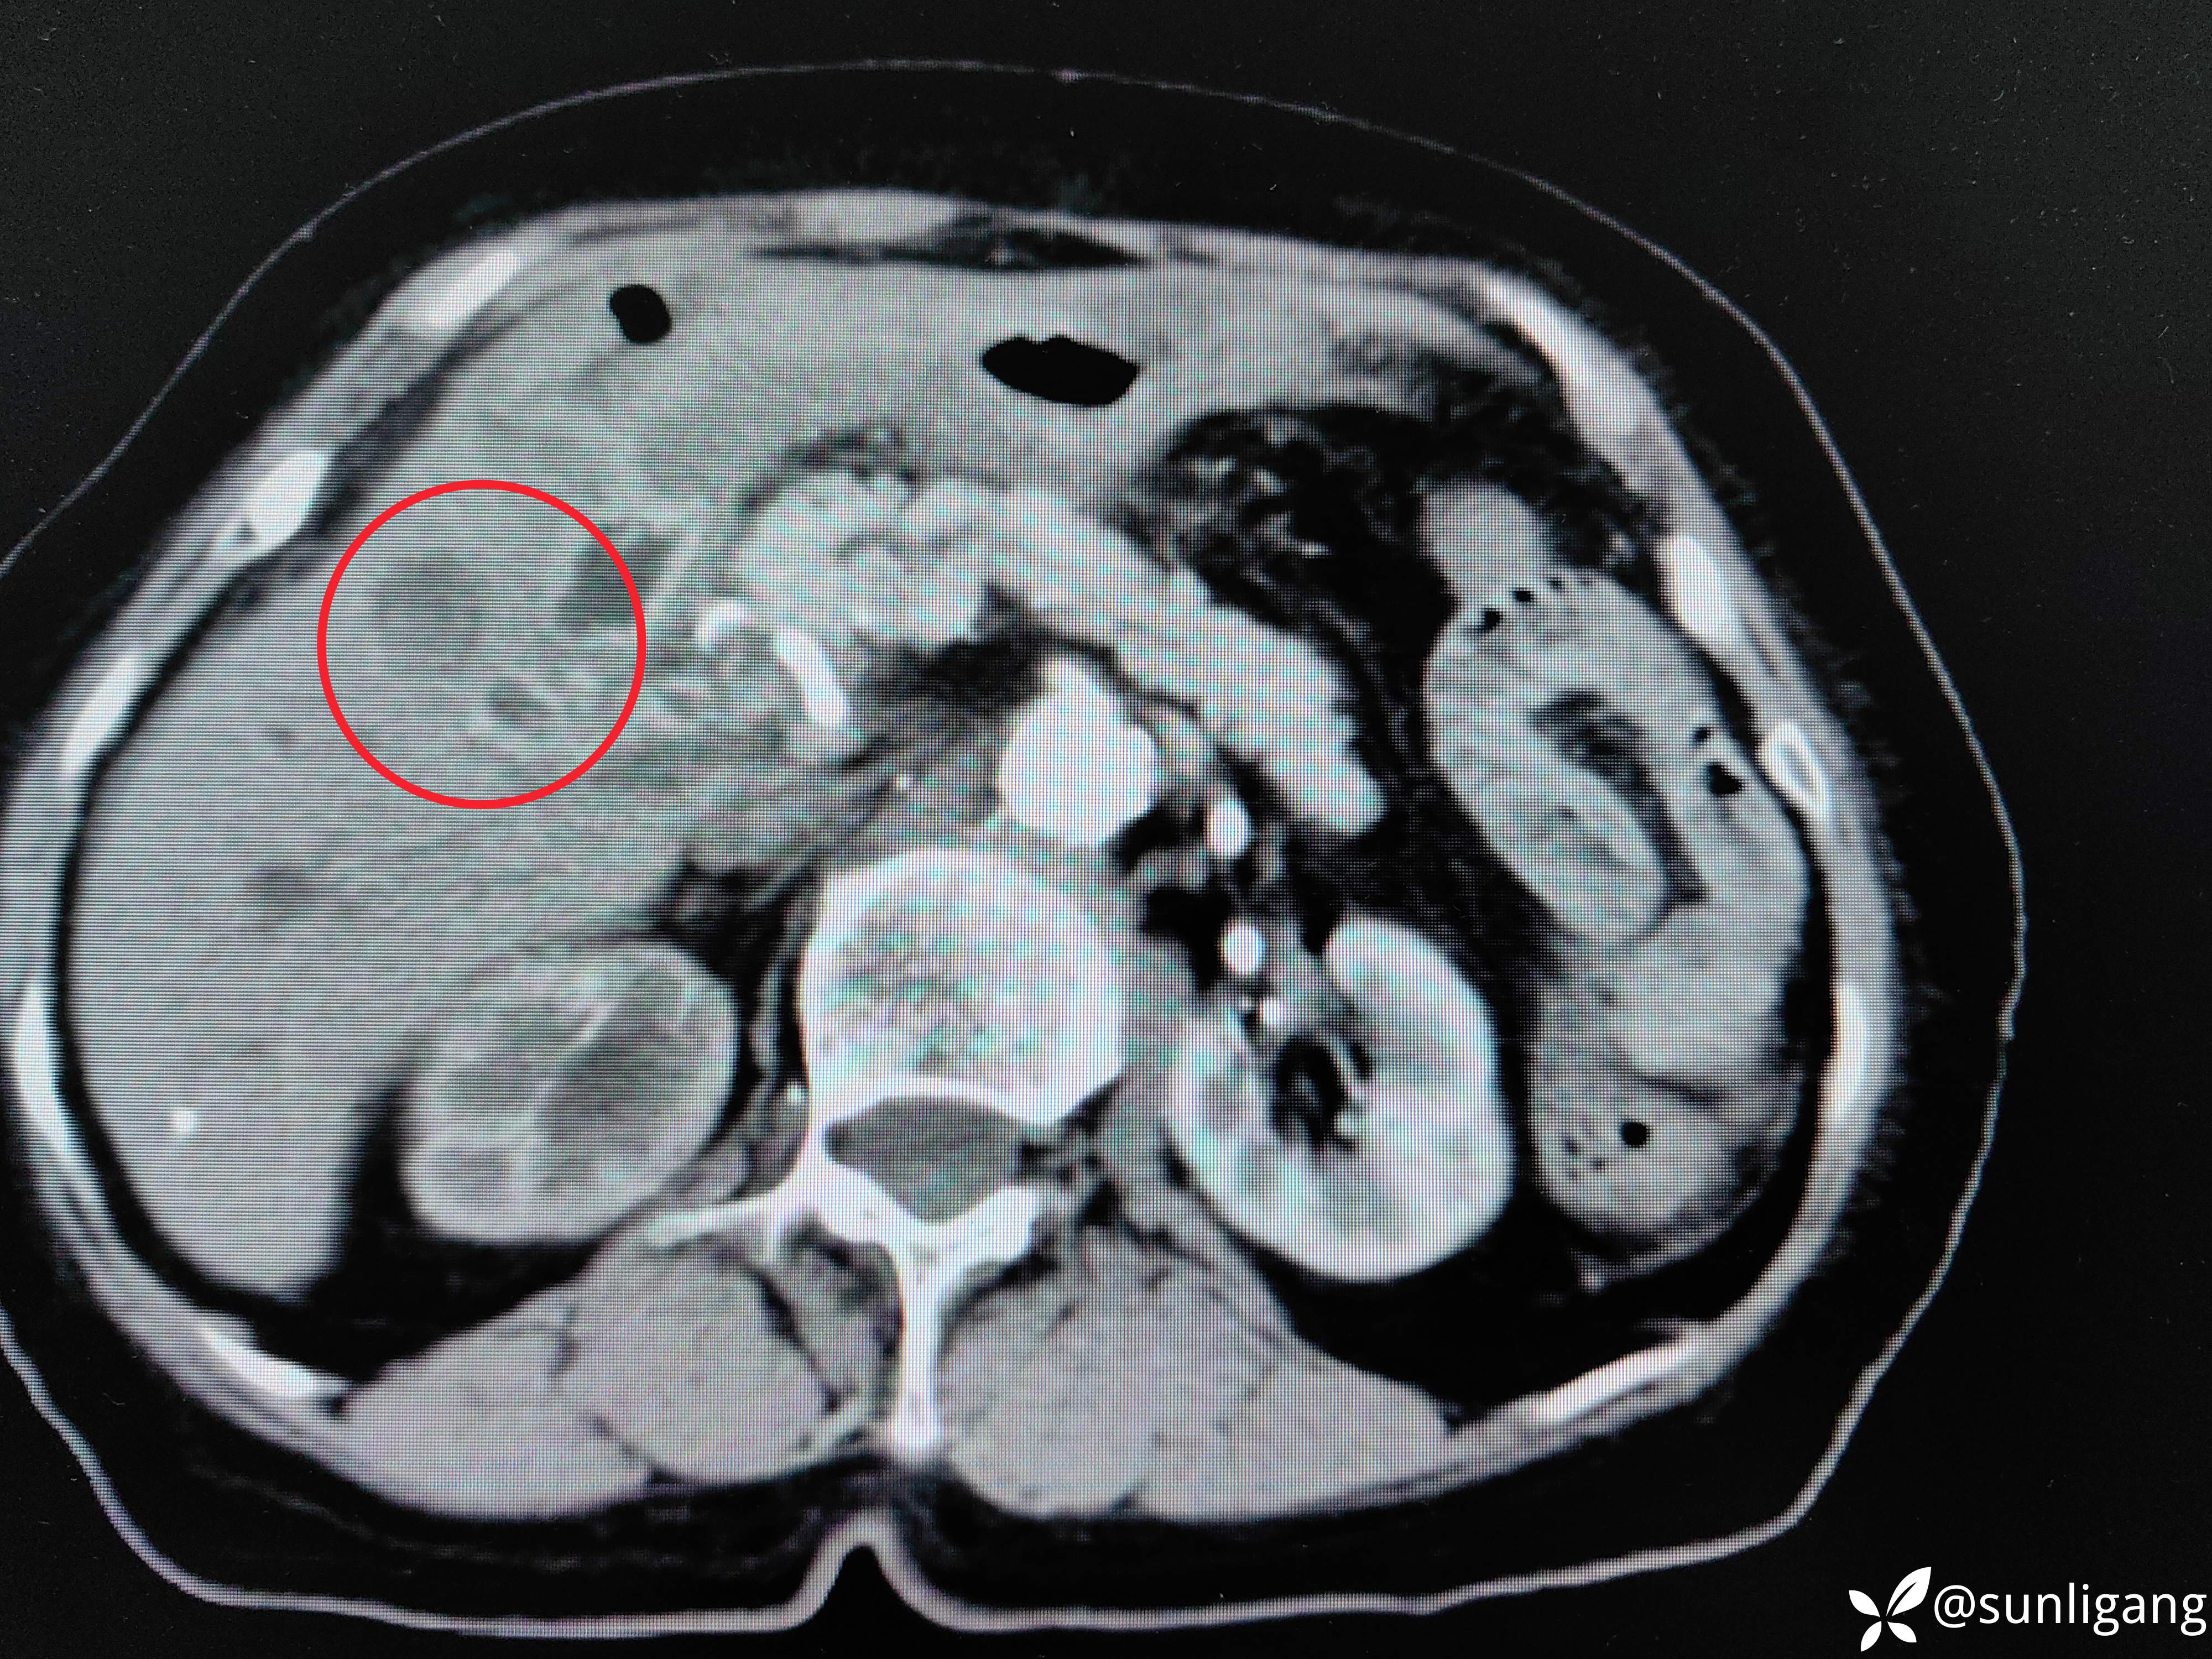

延迟期(可见胃小弯侧胃壁增厚)

增厚的胃后壁,静脉期仍有明显强化

层面继续往下:

胆囊牵拉肝脏,使局部肝脏边缘内陷

胆囊与肝脏间已无明显界限,肝脏边缘内陷

增厚的胆囊壁

局部已无正常组织间隙,如肝与结肠、肝与胃之间,可见到明显的肿物,还有十二指肠憩室